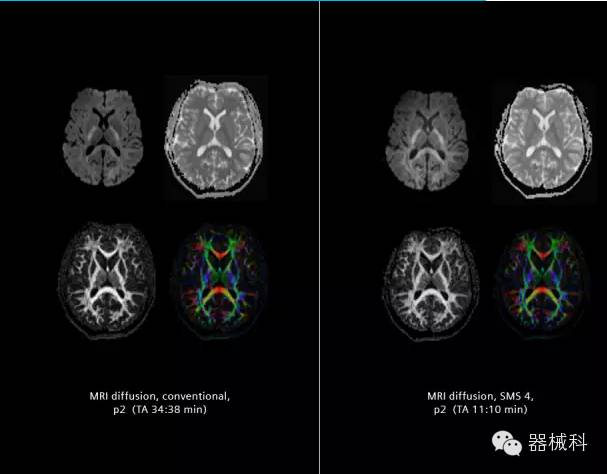

在2015年RSNA上,西門子隆重發(fā)布了Simultaneous Multi-slices 技術(shù)(即同時(shí)多層采集技術(shù),簡稱SMS),這是磁共振掃描技術(shù)中第一次引入“同時(shí)多層”的概念,此概念技術(shù)的發(fā)布,將對未來磁共振成像領(lǐng)域帶來巨大的變革!

SMS技術(shù)可以將原本用于科研的高級成像技術(shù)轉(zhuǎn)化成臨床常規(guī)。

擁有了SMS“同時(shí)多層”采集技術(shù)之后,用戶可以在非常短的時(shí)間內(nèi)完成MR掃描,結(jié)合西門子靜音技術(shù),大大提高患者的舒適性,或在單位時(shí)間內(nèi)采集更多的數(shù)據(jù),也可以得到高精度、高準(zhǔn)確性、大數(shù)量的功能成像數(shù)據(jù),為臨床和科研提供強(qiáng)大的支持。專家認(rèn)為,SMS“同時(shí)多層”采集技術(shù)未來在 提高成像質(zhì)量、外科手術(shù)計(jì)劃、降低術(shù)后神經(jīng)功能缺陷、提高fMRI的時(shí)間采集效率、提高靜息態(tài)功能磁共振數(shù)據(jù)質(zhì)量等方面將帶來深遠(yuǎn)影響,希望該技術(shù)可以盡早面世,引領(lǐng)磁共振進(jìn)入多層時(shí)代!